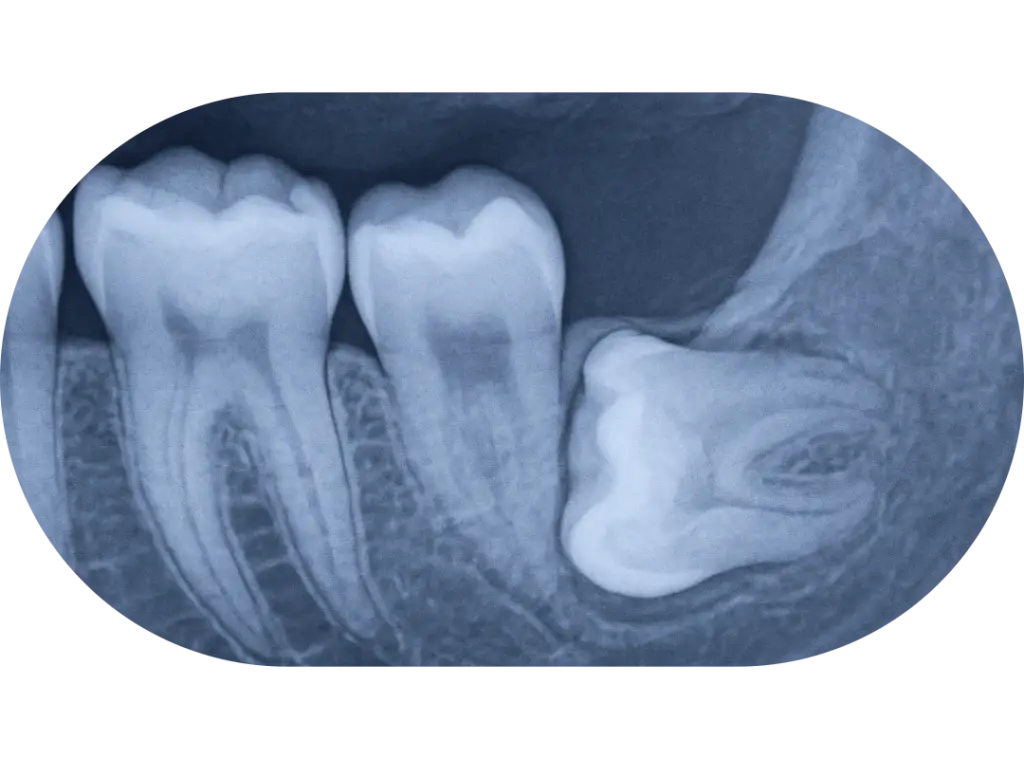

Impacted or Blocked Permanent Teeth

At this stage, children’s jaws are actively developing and they still have a mix of baby teeth and permanent teeth. Because growth is still occurring, we can guide the jaw and tooth eruption patterns more predictably than we can in later adolescence or adulthood.